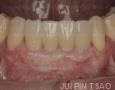

2 Years

3 Years

4 Years

5 Years